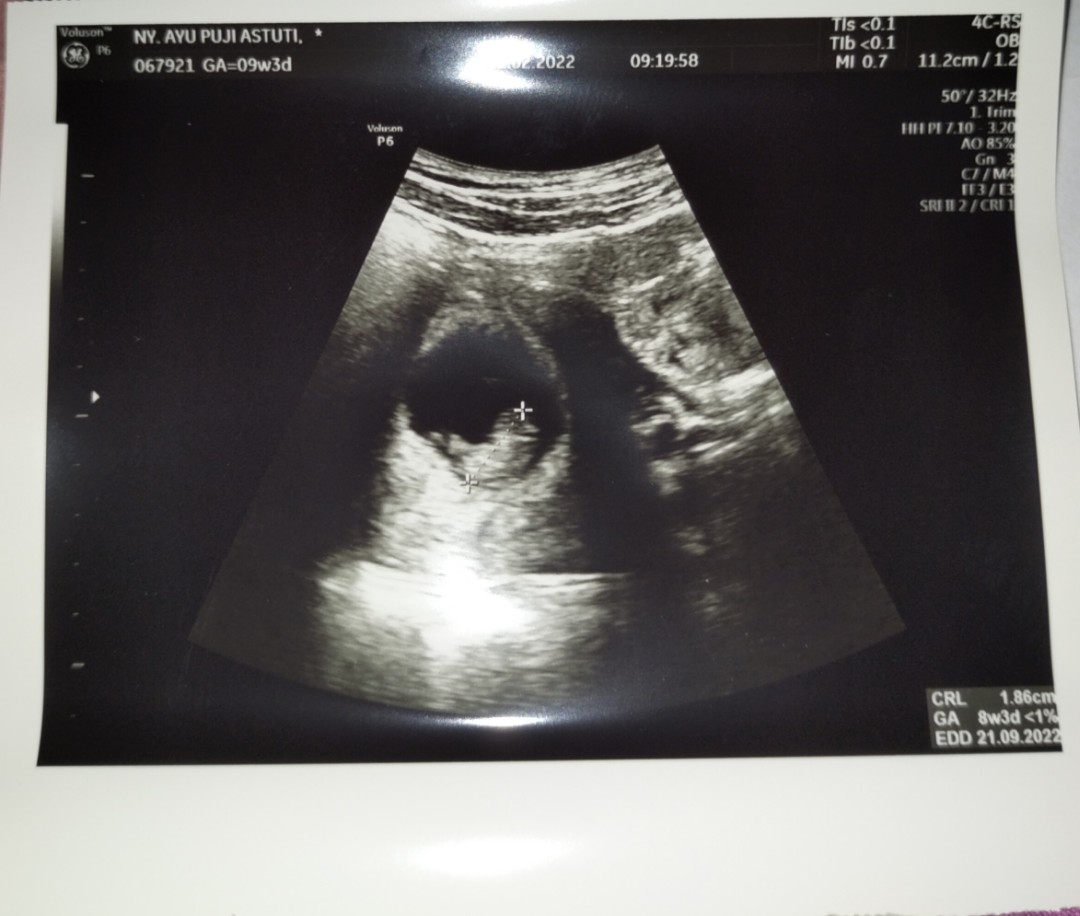

Saya usg pertama di usia kandungan saya 8wek bun,, dan hasil nya alhamdulilah udah ada ddek nya,, dan detak jantung nya sudah bisa di dengarr,, Ini hasil nya bun,,